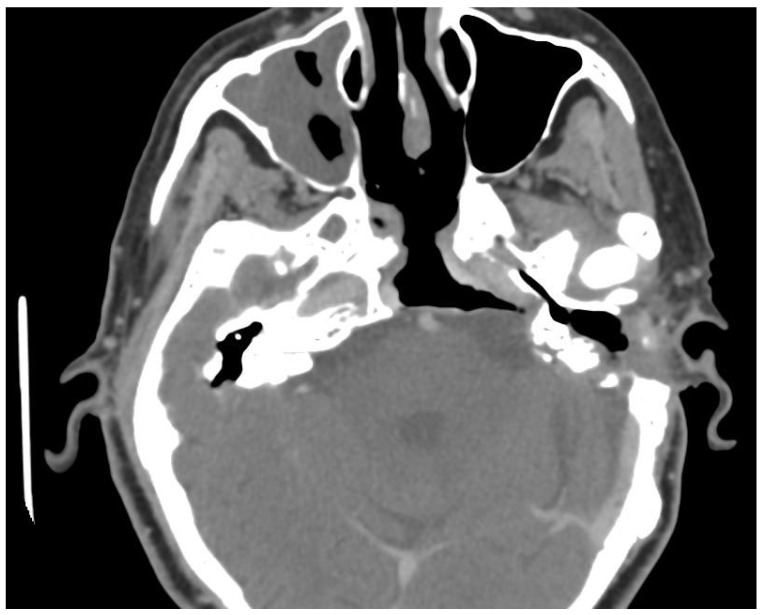

Background and Clinical Significance: Petrous bone cholesteatoma is a rare and complex condition that poses significant challenges in terms of its diagnosis and treatment. This benign yet locally aggressive lesion can cause extensive destruction of the surrounding structures, potentially leading to serious complications. Case Presentation: We present a case of extensive petrous bone cholesteatoma involving nearly the entire skull base. High-resolution CT and MRI were used to assess the extent of the lesion and its relationship with critical neurovascular structures. The cholesteatoma extended from the petrous apex to the clivus, involving the internal auditory canal and Meckel's cave, encasing the internal carotid artery, and compressing the brainstem. The surgical strategy included combined endoscopic transsphenoidal and transclival techniques with a retrolabyrinthine approach. The endoscopic component provided access to the anterior and central skull base regions, whereas the retrolabyrinthine approach allowed us to gain access to the posterior petrous area. Careful dissection was performed to separate the cholesteatoma from the internal carotid artery and the brainstem. Neuromonitoring was performed throughout the procedure to ensure cranial nerve integrity. This combined approach enabled gross total resection, and postoperative imaging confirmed successful tumor removal. The patient's recovery was uneventful, and no new neurological deficits were observed. Conclusions: The successful management of this complex case demonstrates the efficacy and safety of combining endoscopic surgical approaches for extensive skull base cholesteatomas. This multi-corridor approach allows for maximal tumor resection while also minimizing the risks to critical neurovascular structures.